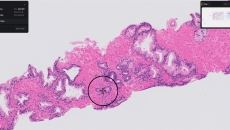

Paige Prostate

Paige receives FDA De Novo clearance for AI to detect prostate cancer

Paige Prostate analyzes digitized biopsy slides and identifies areas that could be cancerous for the pathologist to review further.